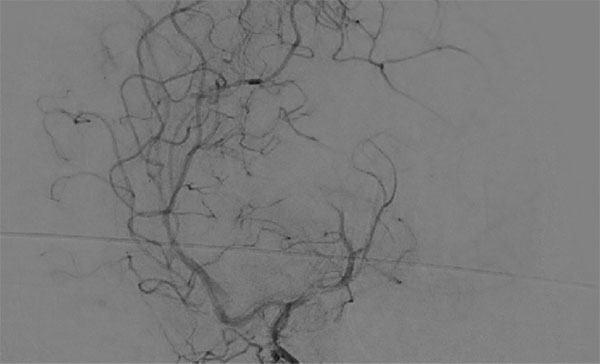

手术再次取栓

图5

图6

诊疗经过:患者取栓术后行NIHSS评分7分,给予改善循环、抗凝等治疗14天后,患者 NIHSS评分为2分,痊愈出院。